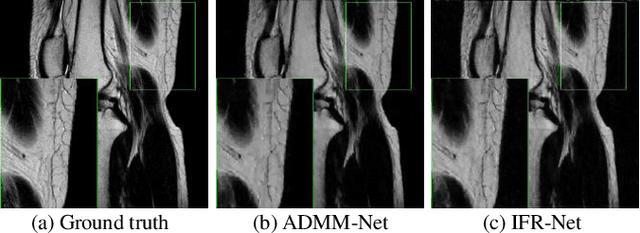

Abstract:To improve the compressive sensing MRI (CS-MRI) approaches in terms of fine structure loss under high acceleration factors, we have proposed an iterative feature refinement model (IFR-CS), equipped with fixed transforms, to restore the meaningful structures and details. Nevertheless, the proposed IFR-CS still has some limitations, such as the selection of hyper-parameters, a lengthy reconstruction time, and the fixed sparsifying transform. To alleviate these issues, we unroll the iterative feature refinement procedures in IFR-CS to a supervised model-driven network, dubbed IFR-Net. Equipped with training data pairs, both regularization parameter and the utmost feature refinement operator in IFR-CS become trainable. Additionally, inspired by the powerful representation capability of convolutional neural network (CNN), CNN-based inversion blocks are explored in the sparsity-promoting denoising module to generalize the sparsity-enforcing operator. Extensive experiments on both simulated and in vivo MR datasets have shown that the proposed network possesses a strong capability to capture image details and preserve well the structural information with fast reconstruction speed.